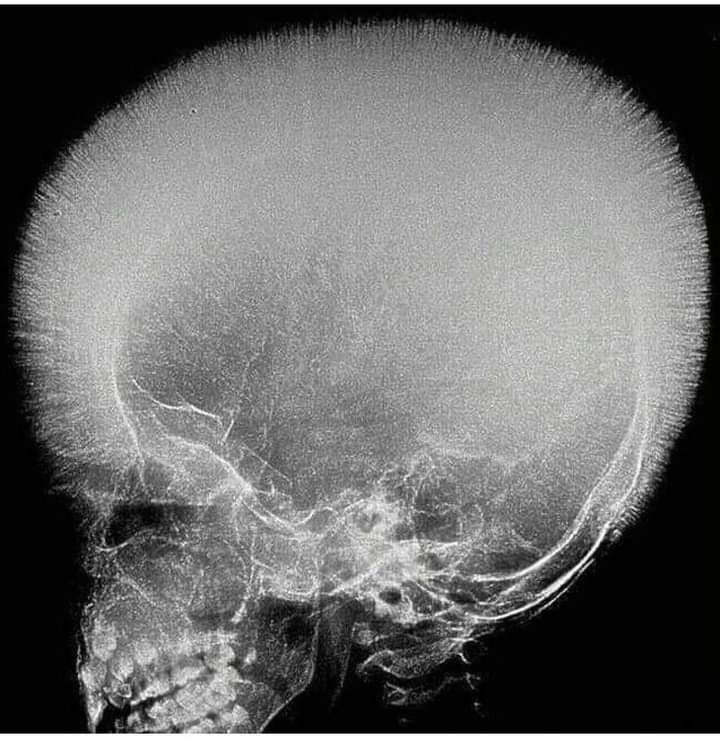

35-year-old Patient presents with hematuria and flank pain and a past history of tuberculosis. NCCT scan of the abdomen is done and given below. What is the urinary bladder in this condition? A. Corkscrew bladder B. Christmas tree bladder C. Thimble bladder D. Putty bladder